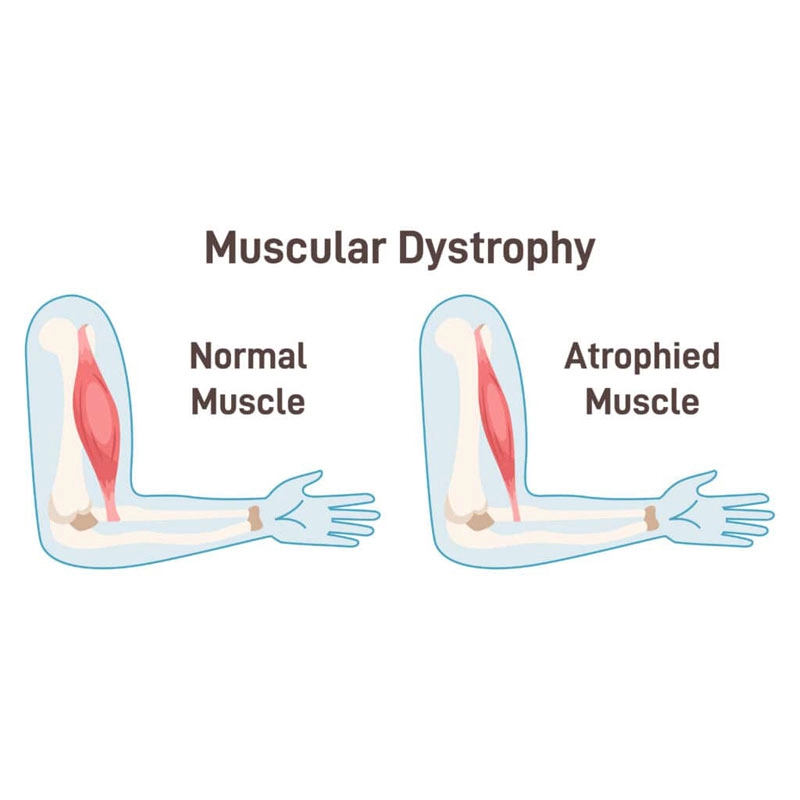

سارکولما یا غشای سلولی عضلانی در این بیماران دچار آسیبهای مکرر میشود و توانایی ترمیم خود را از دست میدهد. میوسیتها یا سلولهای عضلانی به تدریج با بافت فیبروزی و چربی جایگزین میشوند و این فرآیند دژنراتیو باعث کاهش تدریجی قدرت عضلانی میگردد. کینازهای سرمی عضلانی، به ویژه کراتین فسفوکیناز (CPK) در آزمایشهای خون این بیماران به شدت افزایش مییابد که نشاندهنده تخریب فعال بافت عضلانی است.

فرآیند آسیبشناسی دیستروفی عضلانی شامل یک چرخه مخرب است که در آن سلولهای عضلانی آسیب میبینند، تلاش برای ترمیم میکنند، اما به دلیل نقص پروتئینی نمیتوانند به طور کامل بازسازی شوند. با هر چرخه آسیب و ترمیم، تعداد بیشتری از سلولهای عضلانی از بین میروند و با بافت فیبروزی و چربی جایگزین میشوند. این فرآیند منجر به کاهش تدریجی قدرت عضلانی و افزایش ناتوانی میشود.

در برخی بیماران، بزرگ شدن ظاهری عضلات ساق پا دیده میشود که به آن بزرگشدگی کاذب عضله گفته میشود. این وضعیت ناشی از تجمع چربی و بافت همبند در عضله است و به معنی افزایش واقعی قدرت عضلانی نیست.